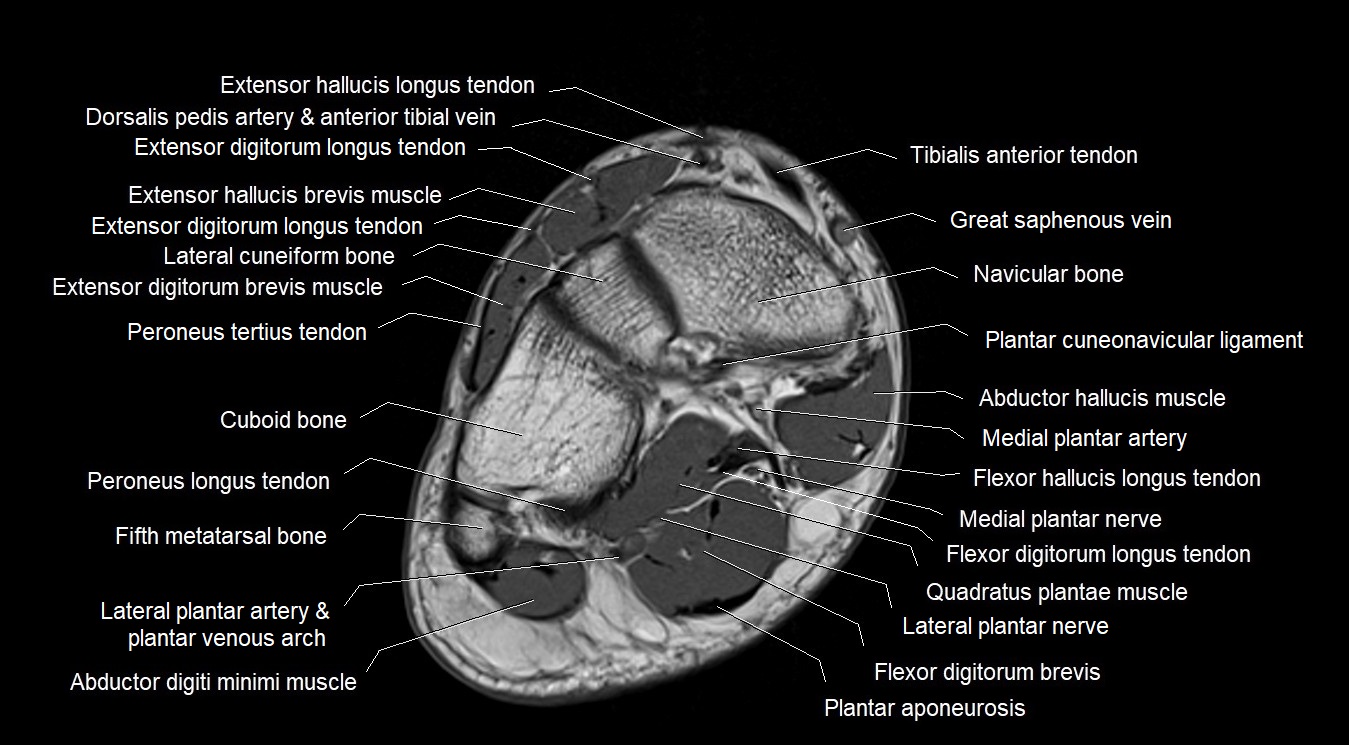

MRI image